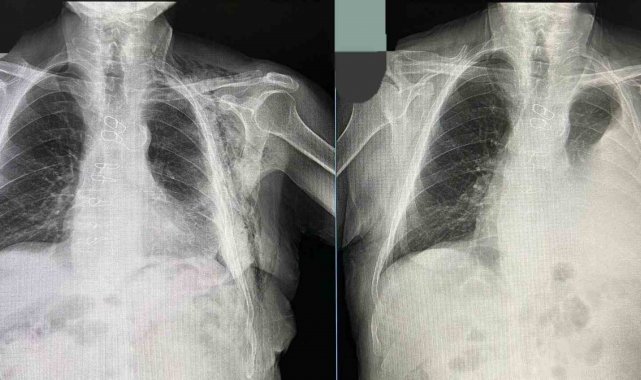

Tüp torakostomiye dirençli efüzyon nedeniyle değerlendirmeye alınan hastaya Göğüs Cerrahisi Uzmanı Op. Dr. Halil Kolcu tarafından kapalı yöntemle akciğeri serbestleme ameliyatı yapıldı.

Başarılı geçen operasyonla hastanın akciğerinin yeniden genişlemesi sağlanırken, sıvı birikiminin önüne geçildi. Hastanın ameliyat sonrası sürecinin sorunsuz ilerlediği ve altıncı günde taburcu edildiği öğrenildi.